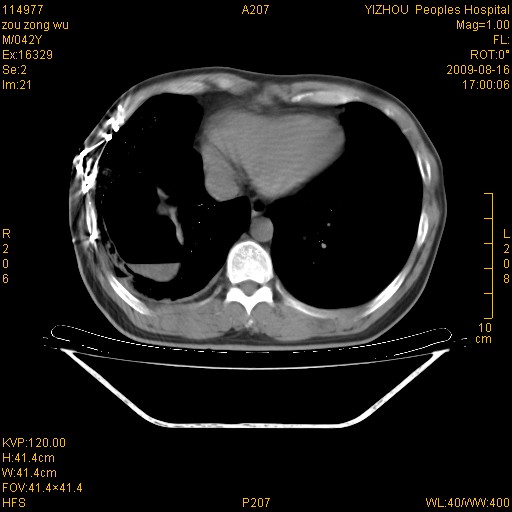

以下是引用zjzjr在2009-8-17 10:42:00的发言:[br]右侧间质性肺炎伴纤维化,右肺下叶肺囊肿伴感染(不除外外伤后引起),右肺野及胸壁软组织\\肝内见多发斑点状,中枪了吧.右侧胸膜肥厚\\粘连.